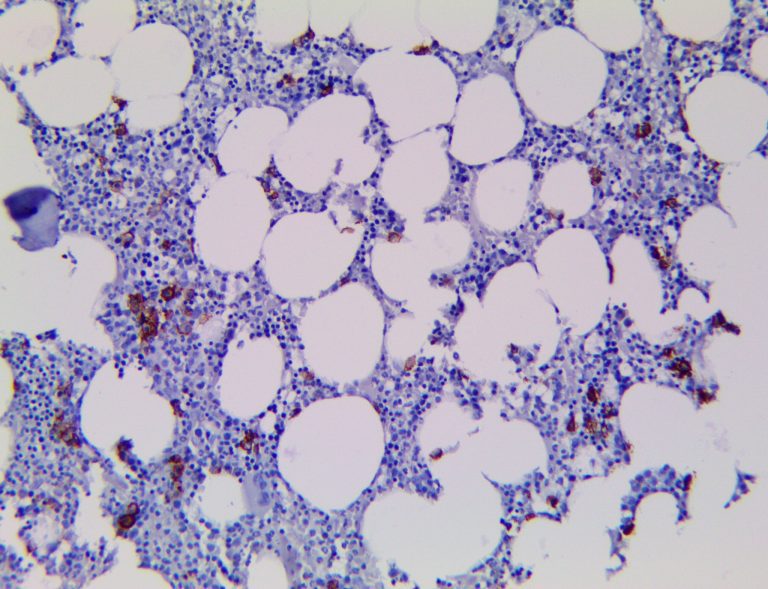

It is the ICU physician who is most likely to witness one of the deadliest manifestations of the abnormal immunological response, the cytokine storm syndrome (CSS). This response is also referred to by some as the cytokine release syndrome (CRS). CSS is characterized by continuous activation and expansion of macrophage and lymphocyte populations, which secrete large amounts of cytokines, causing the cytokine storm. This massive cytokine release is akin to hemophagocytic lymphohistiocytosis (HLH) disease, a syndrome characterized by initial unchecked and persistent activation of cytotoxic T lymphocytes and NK cells.

Clinical and laboratory manifestations of HLH include fever, enlarged liver and/or spleen, neurologic dysfunction, coagulopathy, liver dysfunction, cytopenias (i.e., low levels of erythrocytes, leukocytes, and/or platelets), hypertriglyceridemia, hyperferritinemia, hemophagocytosis, and eventually diminished NK cell activity as the immune system becomes progressively paralyzed. HLH can be familial (primary HLH) or secondary to another disease process (sHLH), such as rheumatic disease, in which it is referred to as macrophage activation syndrome (MAS, characterized by elevated ferritin).